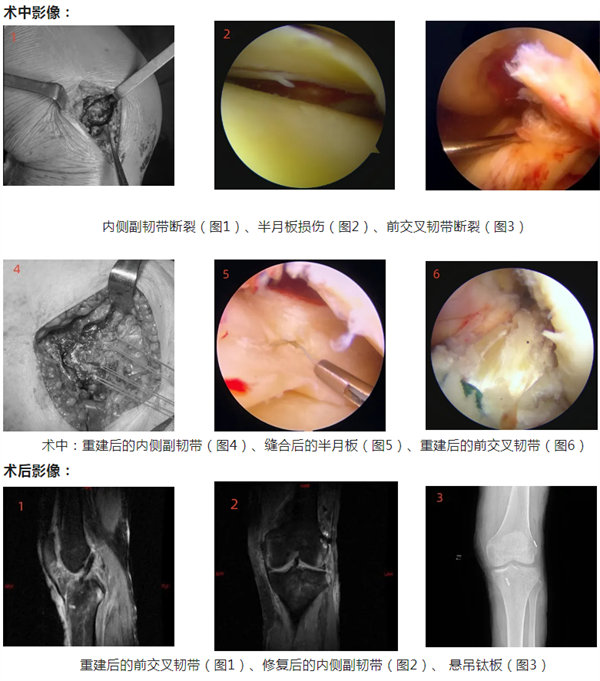

原來,金阿姨因騎電動車時被車撞倒摔傷,隨即出現左膝關節劇烈疼痛,喪失活動能力。來我院骨三科就診,接診醫生為其進行了相關檢查后判斷,她的左膝關節前交叉韌帶斷裂、左膝關節內側副韌帶撕裂、左膝關節內側半月板撕裂、左膝關節外側半月板撕裂,受傷程度診斷符合“膝關節損傷恐怖三聯征”。一旦遭受這種損傷,將導致膝關節穩定性嚴重破壞,進而會引起一系列繼發性損害,并發癥多,關節退變速度將因此成倍增加。

針對她的病情,骨三科主任景斗星組織全科醫生進行了討論,他認為患者需行前交叉韌帶重建,但傳統重建方式(即全長脛骨隧道ACL重建)存在移植物要求高(長度和直徑)、骨質損傷大、內固定不牢固等技術缺陷。建議采取ACL全內重建技術,予以“左側膝關節鏡檢查、半月板探查縫合、取自體肌腱前交叉韌帶全內重建+內側副韌帶斷裂止點重建”手術治療。

在積極完善術前準備后,經過3個小時,手術順利結束,術后患者恢復良好,已經康復出院。